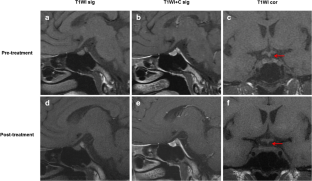

Fig. 1